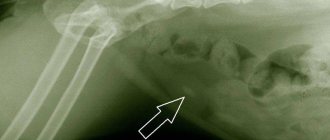

Гной в горле у ребенка, фото обследования

Появление гноя в горле у ребенка без предшествующей выраженной симптоматики нередко может свидетельствовать о наличии инородного предмета в носу или носовых пазухах.

Мама и папа могут заметить, что у ребенка появился неприятный запах изо рта, а при осмотре горла гной можно увидеть по задней стенке. Это свидетельствует о том, что гнойный экссудат стекает в ротоглотку.

Если предмет расположен в носовом ходу низко, то гнойное отделяемое может отходить и через нос, имитируя насморк. Однако выделения будут только из той ноздри, в которой находится предмет. Для насморка одностороннее течение из носа не характерно.